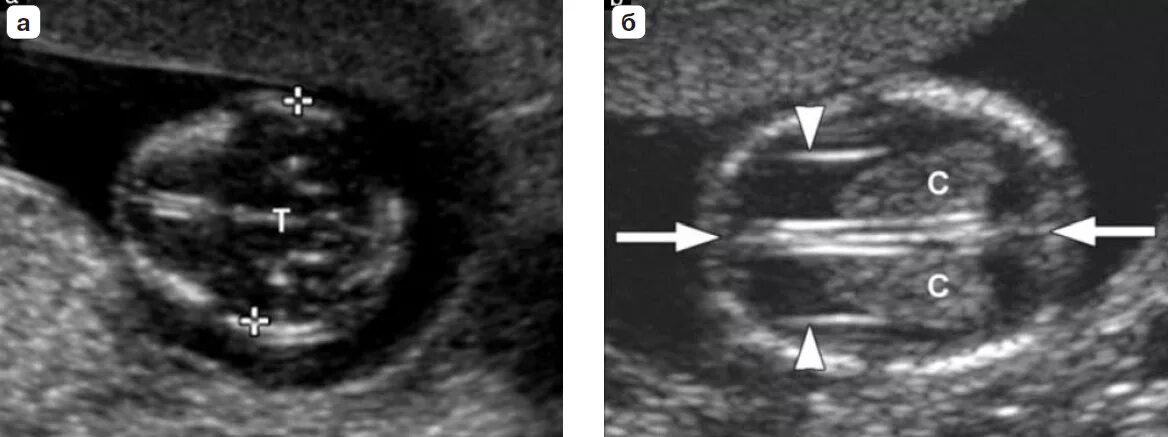

Узи аномалий